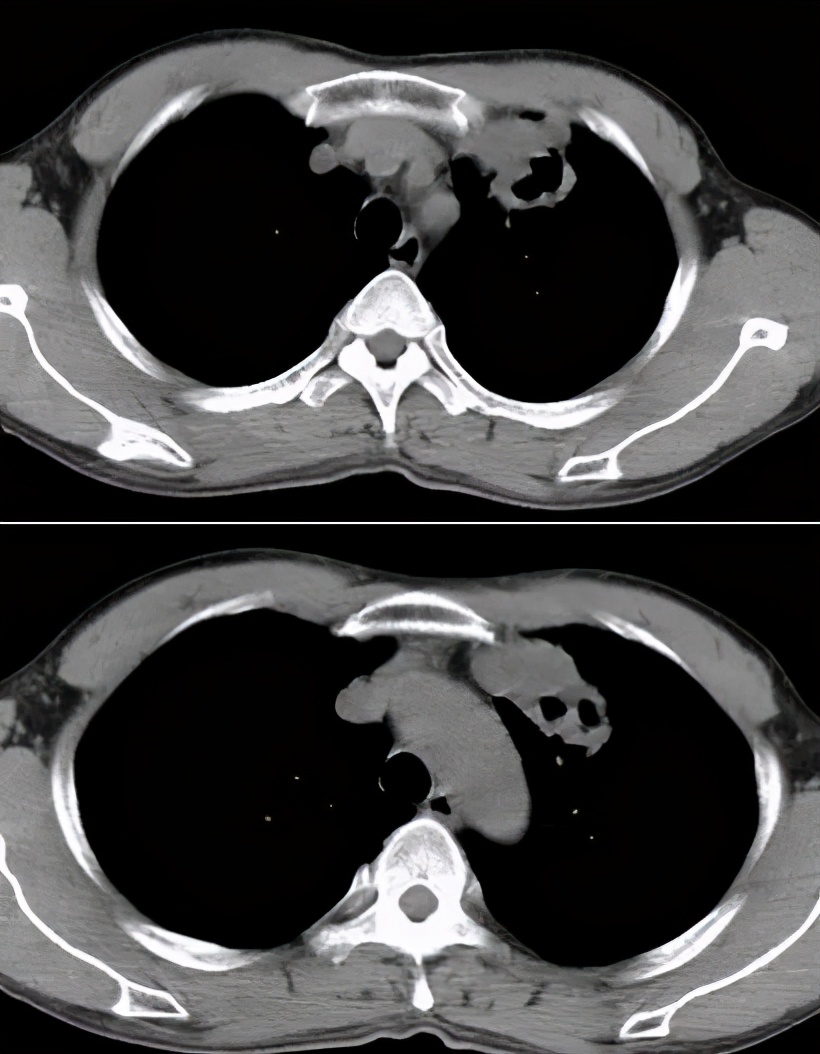

对于ICH的肺结核病影像表现,我与大家分享一些病例

病例1:

68岁,男性,2017年1月入院。主诉:反复发热2月,右侧胸隐痛;现病史:胸部CT示双肺散在炎症,抗感染治疗(头孢菌素、呼吸喹诺酮)后有吸收;但症状反复。

寻常型天疱疮,长期美卓乐、硫唑嘌呤治疗;类固醇性糖尿病。

CRP 196↑ mg/L;白细胞计数 9.12 ×10^9/L 中性粒细胞% 98.2;反复痰找抗酸杆菌(-)。

右侧胸腔穿刺,抽得脓性胸水,胸水涂片见抗酸杆菌4+。

图:2017-1 胸部CT:左肺上叶后段团片影,较前片有所减小;两肺多发炎症,较前片部分吸收;右侧胸膜增厚、胸腔积液,较前片有所增多。

病例2:

男性,42岁。 2008年诊断干燥综合症,当时胸部影像学未见异常。糖皮质激素30毫克/日 ,减量过程中口干症状加重,2009年7月再次全身检查,胸部CT见左上肺尖段软组织影,伴空腔。(似乎存在空洞,有些低密度区,但究竟是不是空洞呢?需要进一步确认。)

病灶穿刺病理:肉芽肿性炎伴坏死,抗酸染色+。

抗痨治疗6月后:

病例3 :

男,50岁,发热1月;骨穿:感染象;胸部CT:右肺阴影,纵膈淋巴结肿大。

这位患者入院时,完全像是白血病化疗过程中出现的改变,那么,会不会是白血病的肺部浸润呢?但是白血病肺部浸润较多见间质的浸润,而这位患者病变呈片状,是实质性的浸润……我们给患者做了骨穿,证实是感染象。

最终痰抗酸染色阳性、血HIV阳性;患者为同性恋。

病例4:

男性,26岁。2015年8月入院,因「咳嗽、咳痰一个半月,胸痛半月,加重伴高热一天」入院。 糖尿病病史8年余,平素血糖控制差,入院时尿酮体+++。

图:胸部CT:右侧液气胸,右肺实变,伴空洞及气液平。

病例5:

男,52岁,溶血性贫血,激素治疗43天。

最初完全按照大叶型肺炎、细菌性肺炎治疗,没有明显效果。最后出现播散,用了机械通气,出现气胸等等。

病例6:

这位患者是急性单核细胞性白血病,化疗2个疗程后出现病症——发热、咳嗽,咳黄痰,很多人会因此想到细菌性肺炎。但事实上,做了气管镜、采样、活检,证实有大量的抗酸杆菌。肺组织活检证实是肉芽肿改变,最后确诊肺结核。

经过治疗以后明显吸收好转:

病例7:

患者是混合性结缔组织疾病,激素治疗6个月后出现发热,肺部病灶明显增多,两侧情况不一样,我们冒了很大风险给他做支气管肺泡灌洗,做刷检、做活检,刷检时也找到了抗酸杆菌,但活检的结果是:既有一般的结缔组织的肉芽肿性改变,同时也看到有结核的干酪样坏死。因为患者是在激素减量过程中出现的症状,所以我们考虑是既有结缔组织疾病,又合并了肺结核。